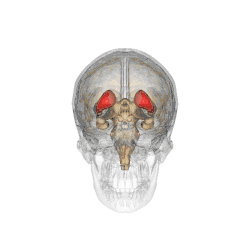

Caudate nucleus

![]() Caudate nucleus (in red) shown within the brain | |

The caudate nucleus is one of the structures that make up the corpus striatum, which is part of the basal ganglia in the human brain.[1] Although the caudate nucleus has long been associated with motor processes because of its relation to Parkinson's disease and Huntington's disease,[2][3] it also plays important roles in nonmotor functions, such as procedural learning,[2] associative learning,[4] and inhibitory control of action.[5] The caudate is also one of the brain structures that compose the reward system, and it functions as part of the cortico-basal ganglia-thalamo-cortical loop.[1]

The caudate nuclei are near the center of the brain, sitting astride the thalamus. There is a caudate nucleus in each hemisphere of the brain. Each nucleus is C-shaped, with a wider "head" (caput in Latin) at the front, tapering to a "body" (corpus) and a "tail" (cauda). Sometimes a part of the caudate nucleus is called the "knee" (genu).[6] The caudate head receives its blood supply from the lenticulostriate artery; the tail of the caudate receives its blood supply from the anterior choroidal artery.[7]